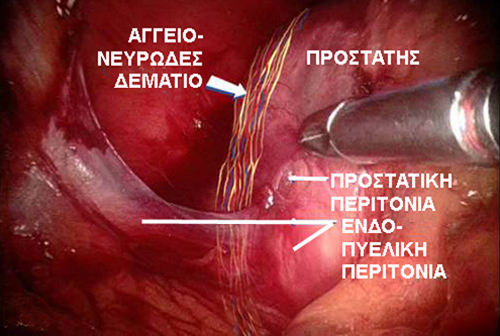

Η ακρίβεια των χειρισμών, η δυνατότητα να υπάρχουν μέσα στην κλειστή κοιλιά του ασθενούς δύο μικροσκοπικά χεράκια που εκτελούν με την ίδια και μεγαλύτερη ευλυγισία και ελευθερία τις κινήσεις του ανθρώπινου καρπού, η μεγεθυμένη και τρισδιάστατη εικόνα και ο έλεγχος που παρέχει το ρομποτικό σύστημα da Vinci συμβάλει στην αφαίρεση του προστάτη, που έχει προσβληθεί από καρκίνο, διατηρώντας ταυτόχρονα τα σπουδαία στυτικά νεύρα και αιμοφόρα αγγεία.

Ο προστάτης απελευθερώνεται από την ουροδόχο κύστη και την ουρήθρα διατηρώντας τα λεπτά στυτικά νεύρα, εφόσον αυτό είναι εφικτό από την έκταση του καρκίνου, με σκοπό να έχει ο ασθενής αυτόματες στύσεις μετά την ανάρρωση από το χειρουργείο.

Σχηματική απεικόνιση σε πραγματική φωτογραφία της εντόπισης του αγγειονευρώδους δεματίου στη πλάγια επιφάνεια του προστάτη έτσι όπως φαίνεται από την πάνω κοιλιακή άποψη του προστάτη.

Οι πυελικοί λεμφαδένες, οι οποίοι μπορεί να έχουν προσβληθεί από καρκίνο, αφαιρούνται, όταν χρειάζεται για να γίνει καλύτερη εκτίμηση της εξάπλωσης του όγκου του προστάτη. Τέλος, η ουροδόχος κύστη συρράπτεται με την ουρήθρα για την αποκατάσταση της συνέχειας της αποχετέτευσης των ούρων. Η θερμική ενέργεια περιορίζεται στο ελάχιστο κατά την διάρκεια της εκτομής του προστάτη για την αποφυγή βλάβης των λεπτεπίλεπτων στυτικών νεύρων και μυών που ελέγχουν την στύση του πέους και την εγκράτεια των ούρων.

- Στυτική δυσλειτουργία: Στην ανοιχτή ριζική προστατεκτομή, η στυτική δυσλειτουργία μπορεί να είναι μία συχνότερη και πιο βασανιστική ανεπιθύμητη κατάσταση συγκρινόμενη με την ακράτεια ούρων ακόμη και να διενεργήθηκε νευροπροστατευτική τεχνική. Αντίθετα με ρομποτική τεχνολογία έχουμε για πρώτη φορά την δυνατότητα ν’ αναγνωρίζουμε με ασφάλεια και να διατηρούμε στο μέγιστο δυνατό βαθμό τα στυτικά νεύρα στις περισσότερες περιπτώσεις ακόμη καλύτερα και πιο αποτελεσματικά σε σύγκριση με το ανοιχτό χειρουργείο. Η επάνοδος της στυτικής λειτουργίας μετά την ριζική προστατεκτομή είναι πολυπαραγοντική, εξαρτάται από πολλούς και διαφορετικούς παράγοντες, όπως την ηλικία του ασθενή, το βαθμό της προηγούμενης σεξουαλικής λειτουργίας, την τεχνική ακρίβεια της νευροπροστατευτικής χειρουργικής τεχνικής και τον χρόνο που πέρασε από το χειρουργείο. Τα μικροσκοπικά και ευαίσθητα στυτικά νεύρα απαιτούν συνήθως 12 με 18 μήνες για ν’ αναρρώσουν πλήρως. Ο ασθενής υποβάλλεται σ’ αυτό το χρονικό διάστημα σε διάφορες θεραπείες για την ταχύτερη αποκατάσταση των φυσιολογικών και αυθόρμητων στύσεων, όπως πχ λαμβάνοντας διάφορα φάρμακα (πχ Viagra, Cialis, Levitra) ή χρησιμοποιώντας αντλίες κενού για πρόκληση στύσεων ή ενδοπεϊκές ενέσεις. Αυτές οι θεραπείες είναι σε περίπτωση πλήρους διατήρησης των αγγειονευρωδών δεματίων προσωρινές και διατηρούν την αιμάτωση στο πέος αναμένοντας την ανάρρωση της λειτουργίας των στυτικών νεύρων.

Στην θεραπεία του καρκίνου του προστάτη τα χιλιοστά κάνουν την διαφορά. Οι νευρικές ίνες και τα αιμοφόρα αγγεία είναι κολλημένα γύρω από τον προστάτη. Για να διατηρηθούν αυτά τα νεύρα πρέπει προσεκτικά να διαχωρισθούν από τον προστάτη προτού αφαιρεθεί αυτός. Για σύγκριση η εξωτερική ακτινοβολία μπορεί να προκαλεί αλλαγές που επεκτείνονται αρκετά χιλιοστά. Σε μία μελέτη ελέγχου νεοτέρας γενεάς ακτινοθεραπείας η μέση διακύμανση της επέκτασης του ακτινοβολημένου πεδίου ήταν 3 χιλιοστά.1 Αυτή η διακύμανση μπορεί προκαλέσει την μεταφορά διαφορετικών ποσοτήτων ενέργειας στα όρια του προστάτη εκεί που βρίσκονται τα στυτικά νεύρα.

Οι ρομποτικοί χειρουργοί χρησιμοποιούν την ακρίβεια, την όραση και τον έλεγχο που εξασφαλίζει το σύστημα da Vinci για να αφαιρέσουν τον καρκινωματώδη προστάτη διατηρώντας τα σημαντικά νεύρα και αιμοφόρα αγγεία.

Σεξουαλική λειτουργία

Ο προστάτης περιβάλλεται από λεπτά στρώματα νεύρων που υποστηρίζουν την στυτική λειτουργία. Πολλοί ασθενείς είναι υποψήφιοι για μία νευροπροστατευτική προστατεκτομή, αφαιρώντας ριζικά τον καρκινωματώδη προστάτη αλλά διατηρώντας στον μέγιστο βαθμό τα στυτικά νεύρα.